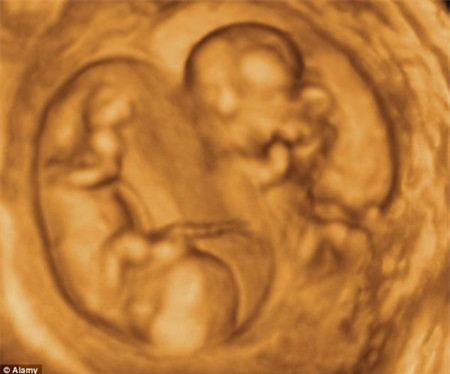

Đa thai cùng trứng: Là hiện tượng trứng sau khi được thụ tinh, tách làm đôi trong giai đoạn hợp tử rồi phát triển thành 2 hoặc nhiều phôi. Hai hoặc nhiều cá thể khi phát triển sẽ giống nhau về hình thức, gene và kháng nguyên.

Đa thai cùng trứng thường xảy ra ở giai đoạn phôi nang, khoảng cuối tuần thứ nhất và chia đôi mầm phôi thành hai hoặc nhiều phôi. Hệ quả là hai hoặc nhiều mầm phôi với các túi ối riêng, nhưng chỉ có một túi đệm và một bánh rau (nhau) chung.

Nếu sự phân chia diễn ra sớm khoảng một đến ba ngày sau khi thụ thai thì các bé sẽ phát triển riêng biệt và đồng đều nhau.

Nếu sự phân chia diễn ra muộn hơn, từ khoảng ngày thứ 5 đến ngày thứ 10 sau khi thụ thai thì hai bé vẫn phát triển riêng biệt nhưng không đồng đều nhau, một thai có thể phát triển to béo, đôi khi phù nề, tăng hồng cầu; trong khi thai còn lại thì còi cọc, thiếu máu, thậm chí có thể teo và chết đi. Thường có sự thông thương tuần hoàn giữa hai thai nhi, do đó máu đến nuôi có thể dồn hẳn về một thai nhi, trong khi thai kia thì rất ít hoặc không được nuôi dưỡng.

Trường hợp mầm phôi tách đôi muộn (trong tuần lễ thứ 2) sẽ dẫn đến đa thai cùng trứng chỉ có một túi ối và một túi đệm. Các trường hợp này thai ít khi sống được do dây rốn rối nhiều, tuần hoàn máu qua dây rốn bị nghẽn và một hay cả hai thai sẽ chết. Tỷ lệ đa thai cùng trứng có một ối chiếm tỷ lệ 1/4 trong tổng số các trường hợp song thai cùng trứng.